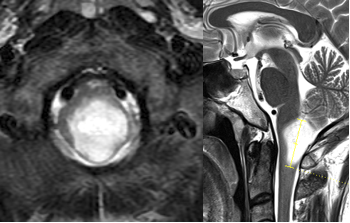

36 岁男性,主诉左侧全身感觉障碍 4 个月,伴轻度偏侧肢体无力。MRI显示延髓下部有一几乎无强化、信号均匀、占位性病变,并向下延伸累及颈髓。患者同意手术,目标为最大限度减瘤并获取确切组织病理学诊断。

术前MRI

幸运的是,手术效果非常好,未出现新的神经功能障碍。组织病理学证实为高级别胶质瘤,WHO III 级,未检出 H3F3A 或 IDH1 突变;无 1p/19q 联合缺失,p53 蛋白无高表达,O6-甲基鸟嘌呤-DNA 甲基转移酶(MGMT)启动子未甲基化。

术后MRI

术后患者接受局部放疗联合替莫唑胺化疗。术后 1 年未见肿瘤进展,生活自理。巴教授对他进行了几年的随访。经过放射治疗和靶向化疗后,他的状况仍然很好。